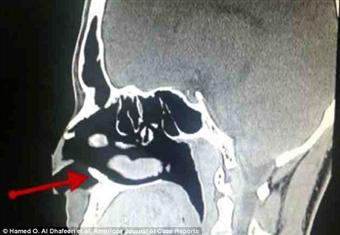

ستشفى الملك فهد العسكري